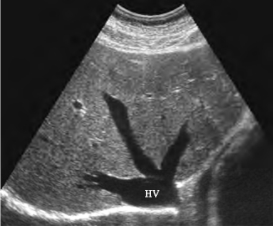

1.27.3三、正常超声表现